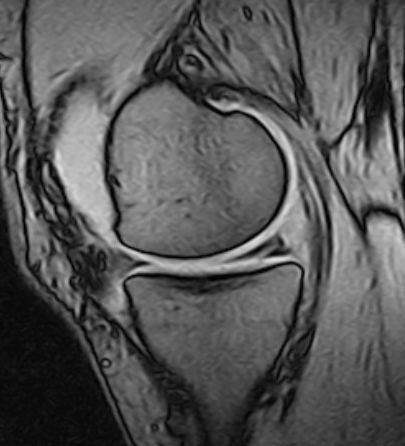

Imidlertid er degenerative meniskrupturer ofte asymptomatiske og kan framstå som tilfeldige funn på MR uten klinisk betydning (20). Rupturene oppstår i degenerert vev med redusert vanninnhold, færre elastiske fibre og økt stivhet, der aksial belastning gir skjærekrefter som river over forbindelser mellom kollagene fibre. Meniskens fasong endres og dens beskyttende funksjon i forhold til leddbrusken blir redusert (21). Rupturene beskrives som komplekse (flere rupturlinjer), horisontale (figur 1) eller flappformede og sitter oftest i bakre del av mediale menisk.

Traumatiske meniskskader ses oftest hos yngre aktive personer og er ofte høyenergiskader, ikke sjelden assosiert med skade av fremre korsbånd (23). Typiske traumatiske rupturer kan være «bøttehankformede» (longitudinelle, vertikale (figur 2, figur 3) og kan ligge innslått mot eminensene), radiale, eller flappformede. Innslåtte bøttehankrupturer kan gi både ekstensjons- og fleksjonsinnskrenkning, og tidlig reponering og sutur er indisert for å hindre skrumpning og destruksjon av meniskvevet.